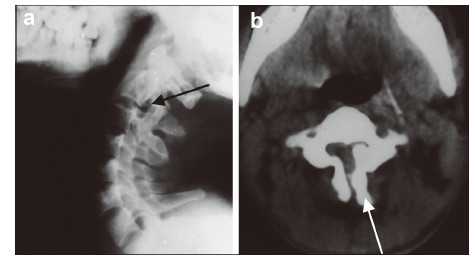

2 Case reports 2.1 Case 1 A 21‐year‐old woman sustained an extension injury in a traffic accident 1 month before admission. Physical examination revealed a limited range of neck motion due to posterior neck pain. The neurologic examination was normal. Palpation of her neck revealed severe tenderness in the upper cervical spine. Lateral view plain radiography identified a hypoplastic articular mass at C3 (Figure 1). Iodine contrast revealed a narrowed spinal canal at C3 on computed tomography (CT). The lateral mass at C3 was discontinuous and typical features of spina bifida were revealed. The surfaces of the spondylolysis were smooth,suggesting a chronic process. Spinal cord compression was definitive,while spondylolisthesis was not observed. The compression was located mainly at the posterior column and instability was not present; posterior decompression was performed,and the symptoms were relieved after surgery.

| Figure 1 A 21‐year‐old woman presented with bilateral C3 spondylolysis.(a) Lateral view plain radiography showing a cleft of the articular pillar,with a bow‐tie configuration (black arrow). (b) On CT,the lateral mass at C3 was discontinuous,with a typical features of spina bifida (white arrow),and was well‐corticated (black arrow). |